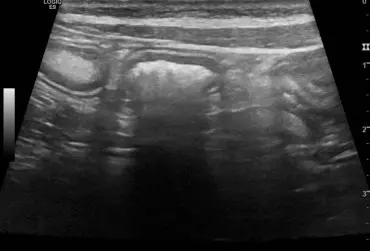

Zespół gruczolakoraka torbielowatego nerek i guzków włóknistych skóry u owczarka niemieckiego – opis przypadku

U 8-letniego niekastrowanego owczarka niemieckiego wykryto obecność kilku guzków skórnych widocznych na kończynach i na nosie. Badanie cytologiczne nie było jednoznaczne. W badaniu histopatologicznym jednego z usuniętych guzków stwierdzono obecność masy kolagenowej z niewielką ilością komórek zajętych głębokim, ropnym zapaleniem skóry. Po roku wykonano badanie ultrasonograficzne układu moczowego z powodu krwiomoczu i pogorszenia się stanu ogólnego psa. Wykryto liczne torbiele w obu nerkach o nietypowej strukturze. Na podstawie wyników badań postawiono rozpoznanie zespołu gruczolakoraka torbielowatego nerek i guzków włóknistych skóry (ang. renal cystadenocarcinoma and nodular dermatofibrosis – RNCD).